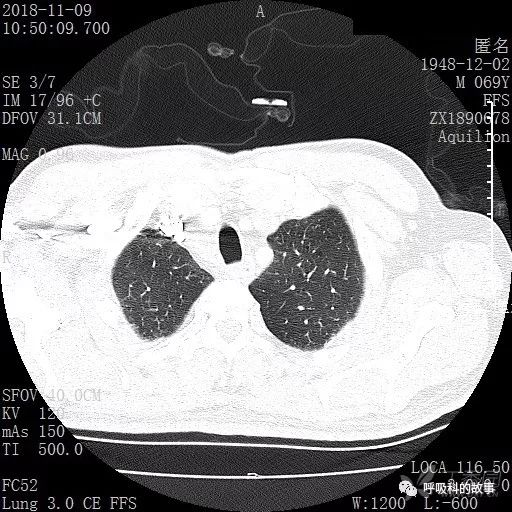

胸部增强CT示右肺门占位伴远端阻塞性肺炎,纵膈、右肺门、右侧颈根部、右侧腋下及肝门部肿大淋巴结。两侧胸腔少量积液。

肺窗CT